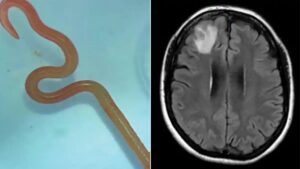

Un vierme care, de obicei, locuiește în pitoni, s-a aciuit în creierul unei femei. Parazitul viu, de 8 centimetri lungime,...